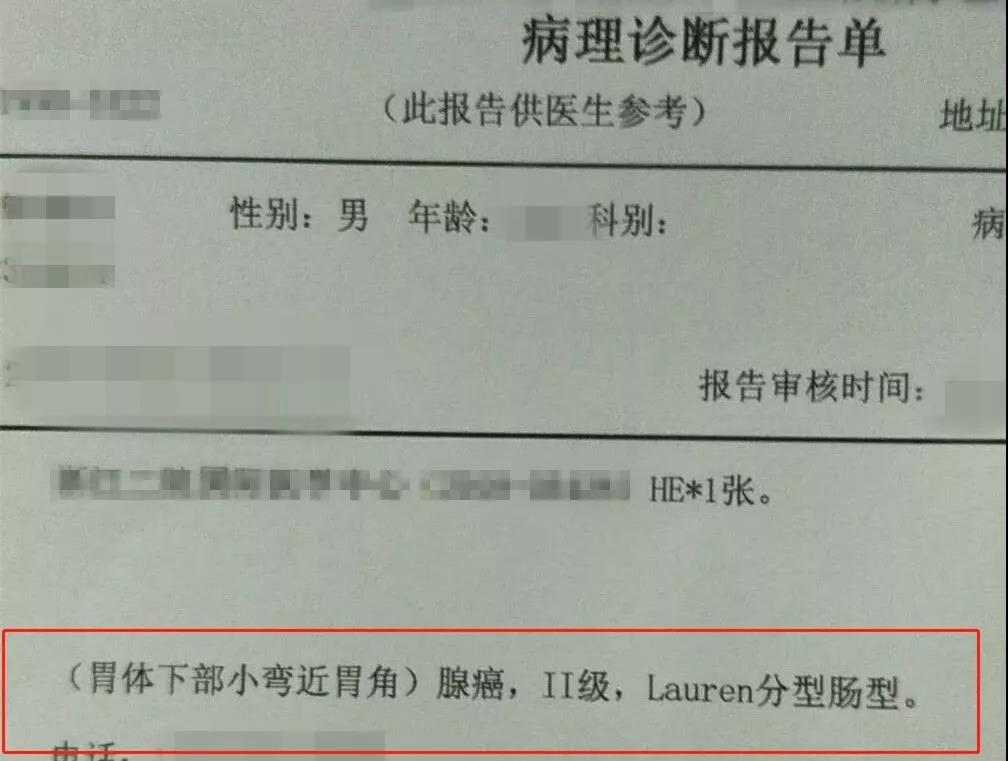

患者小王是一个年仅26岁的小伙子,2个月前因为纳差、反酸、烧心、恶心呕吐,求诊于当地医院。当地医院安排做了胃镜检查。

当时胃镜检查也没有发现明显的问题,而且医生还取了活检,病理报告也是慢性炎症,并没有什么特别的情况。于是医生按照慢性胃炎和消化不良给开了一些胃药。

这是一种高度恶性的胃癌,具有隐蔽性强、侵袭力强、恶性程度高、发展快而臭名昭著;而且对化疗很不敏感,进展期的预后极差。

因为一般的肠型胃癌,是在胃粘膜上皮生长,胃镜进去,就一览无余,很容易发现;

胃印戒细胞癌被归类为弥漫型癌,属于未分化癌的一种(癌的病理学分类,分化越好,预后越好,比如高分化好于中分化和低分化,未分化最差)。

普遍认为印戒细胞癌是一种恶性程度极高的一种胃恶性肿瘤,与常见的肠型胃癌相比,其预后很差,5年生存率为18.4%-44.1%。

另外,胃印戒细胞癌的发病年龄明显早于胃腺癌,发病峰值集中于41-50岁,20来岁、30来岁的也很常见;大多数年轻胃癌患者,多是弥漫性胃癌。